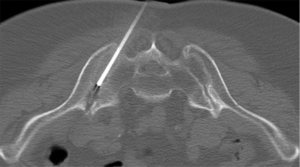

Sacroiliac joint interventions comprise biopsy, aspiration or injection. Percutaneous procedures can be performed using CT, ultrasound or fluoroscopy although CT guidance is the preferred method. In suspected infective sacroiliitis, CT can accurately guide joint aspiration of joint fluid (Figure 24). If no aspirate is obtained, flushing the joint with normal saline and aspirating this saline will increase the likelihood of obtaining a positive culture. If no sacroiliac joint fluid can be obtained even with saline flushing, as in, for example, tuberculous sacroiliitis, para-articular bone biopsy can help confirm or exclude infection (Figure 25). CT can also be used to guide pigtail insertion into abscesses related to infective sacroiliitis (Figure 26).